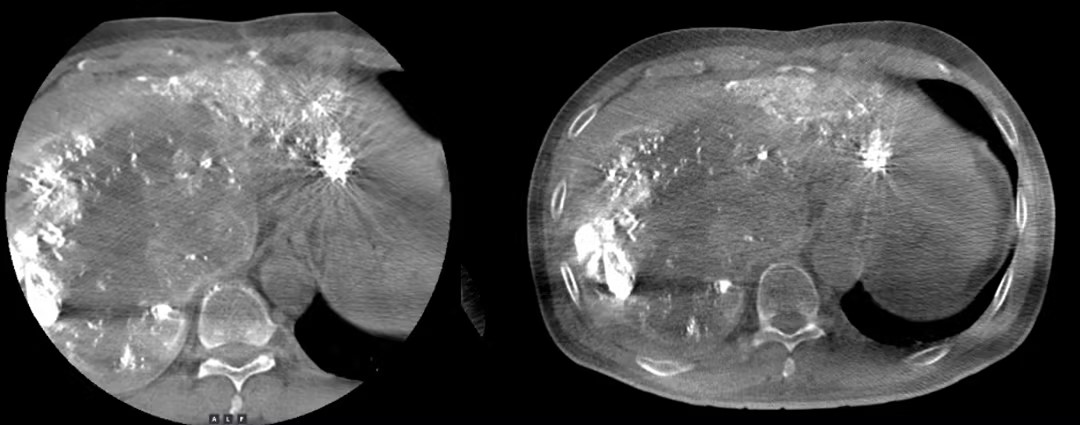

临床图像对比: 大FOV锥束CT VS 常规CBCT

过去,由于FOV(即画幅)尺寸有限,传统设备需转动好几下才能照尽肝脏,宛如“盲人摸象”一点点获取局部认知而后拼凑出全貌。“联影DSA有强大的大FOV锥束CT。在大画幅的帮助下,机器转一次就能看到整个肝脏,一次性把病灶暴露在眼前,治疗精准度和效率自然大幅提高了。”颜主任对大FOV提供的宽阔治疗视野倍感欣喜,同时指出了这一进步为患者带来的安全价值与心灵抚慰。“少检查一次、少做一次手术意味着少吃一次辐射,对患者来说肯定是更安心的。”基于“以人为本”开拓创新值域与视野,令医者和患者均能受益,才是真正从本质上诠释“医”的价值。全新视域下,技术领航的不仅仅是人体内部结构,亦是“生的方向”。与癌的对抗是一场伴随全人类生命周期的未竟之战,肉眼可见的,这场战役还在不断升级。面对强敌,以更精深、更尖端的医疗科技提气自振,是致胜的秘密武器。